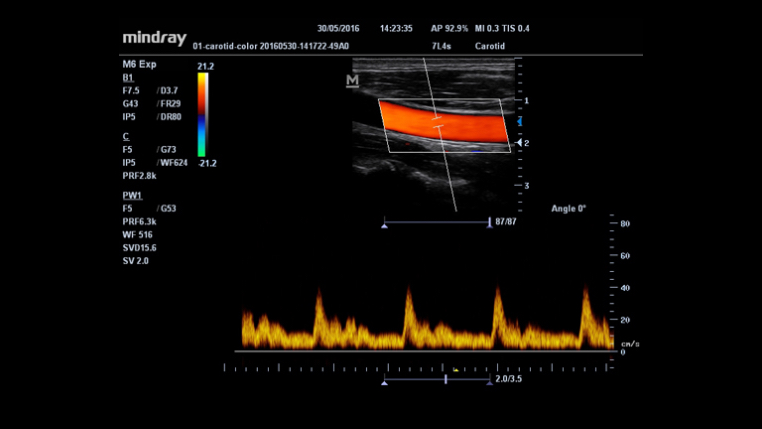

IMT(Intima-Media Thickness)

?? ? ?? ? ?? ? ??? ?? ???? ??? ???? ??? ?????.

Smart Track

?????? ??? ??: ??? ??? ????? ???? ??? ???? ??? ?? ?? ??? ??? ??????.